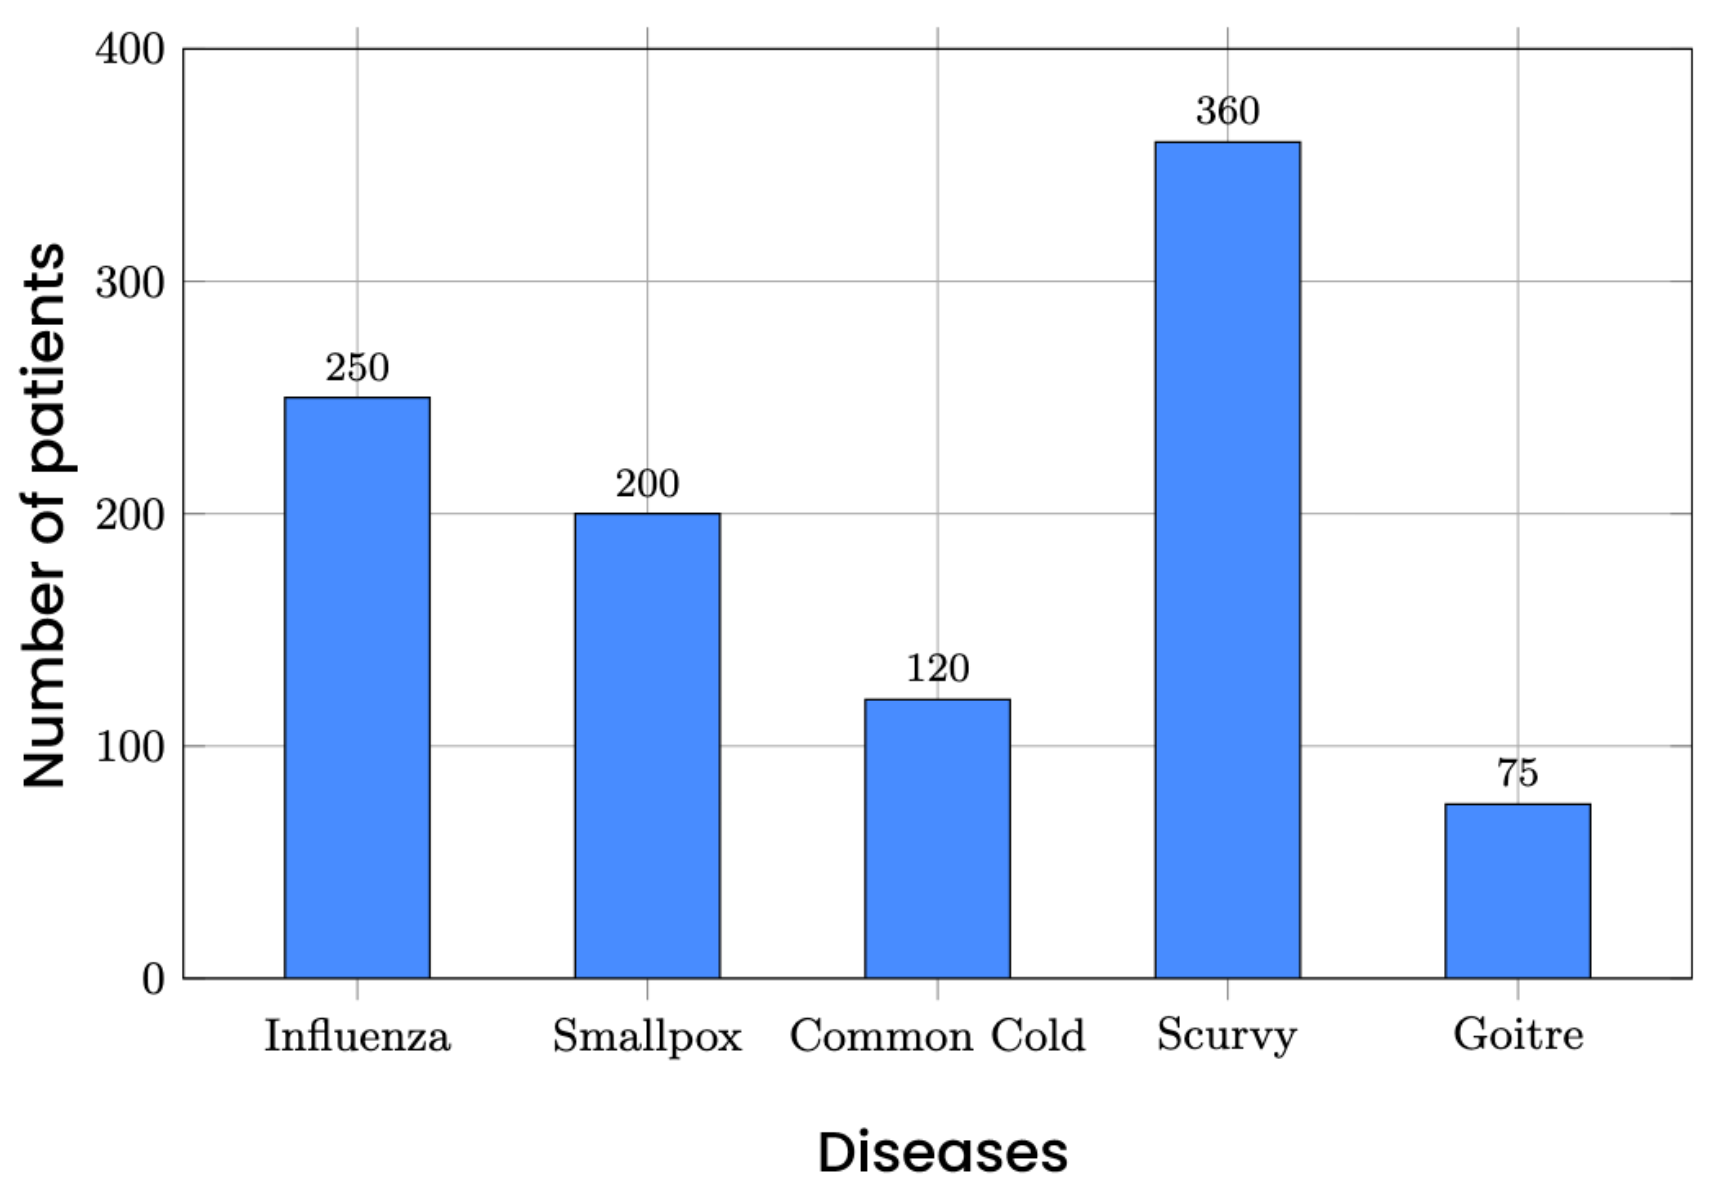

Find the mode in the given bar chart.

|

No changes |

Rationale: The question text and the image contain no Australian-specific spelling, terminology, units, or cultural references. The bar chart uses universal academic grading (A-E) and standard mathematical terminology. |